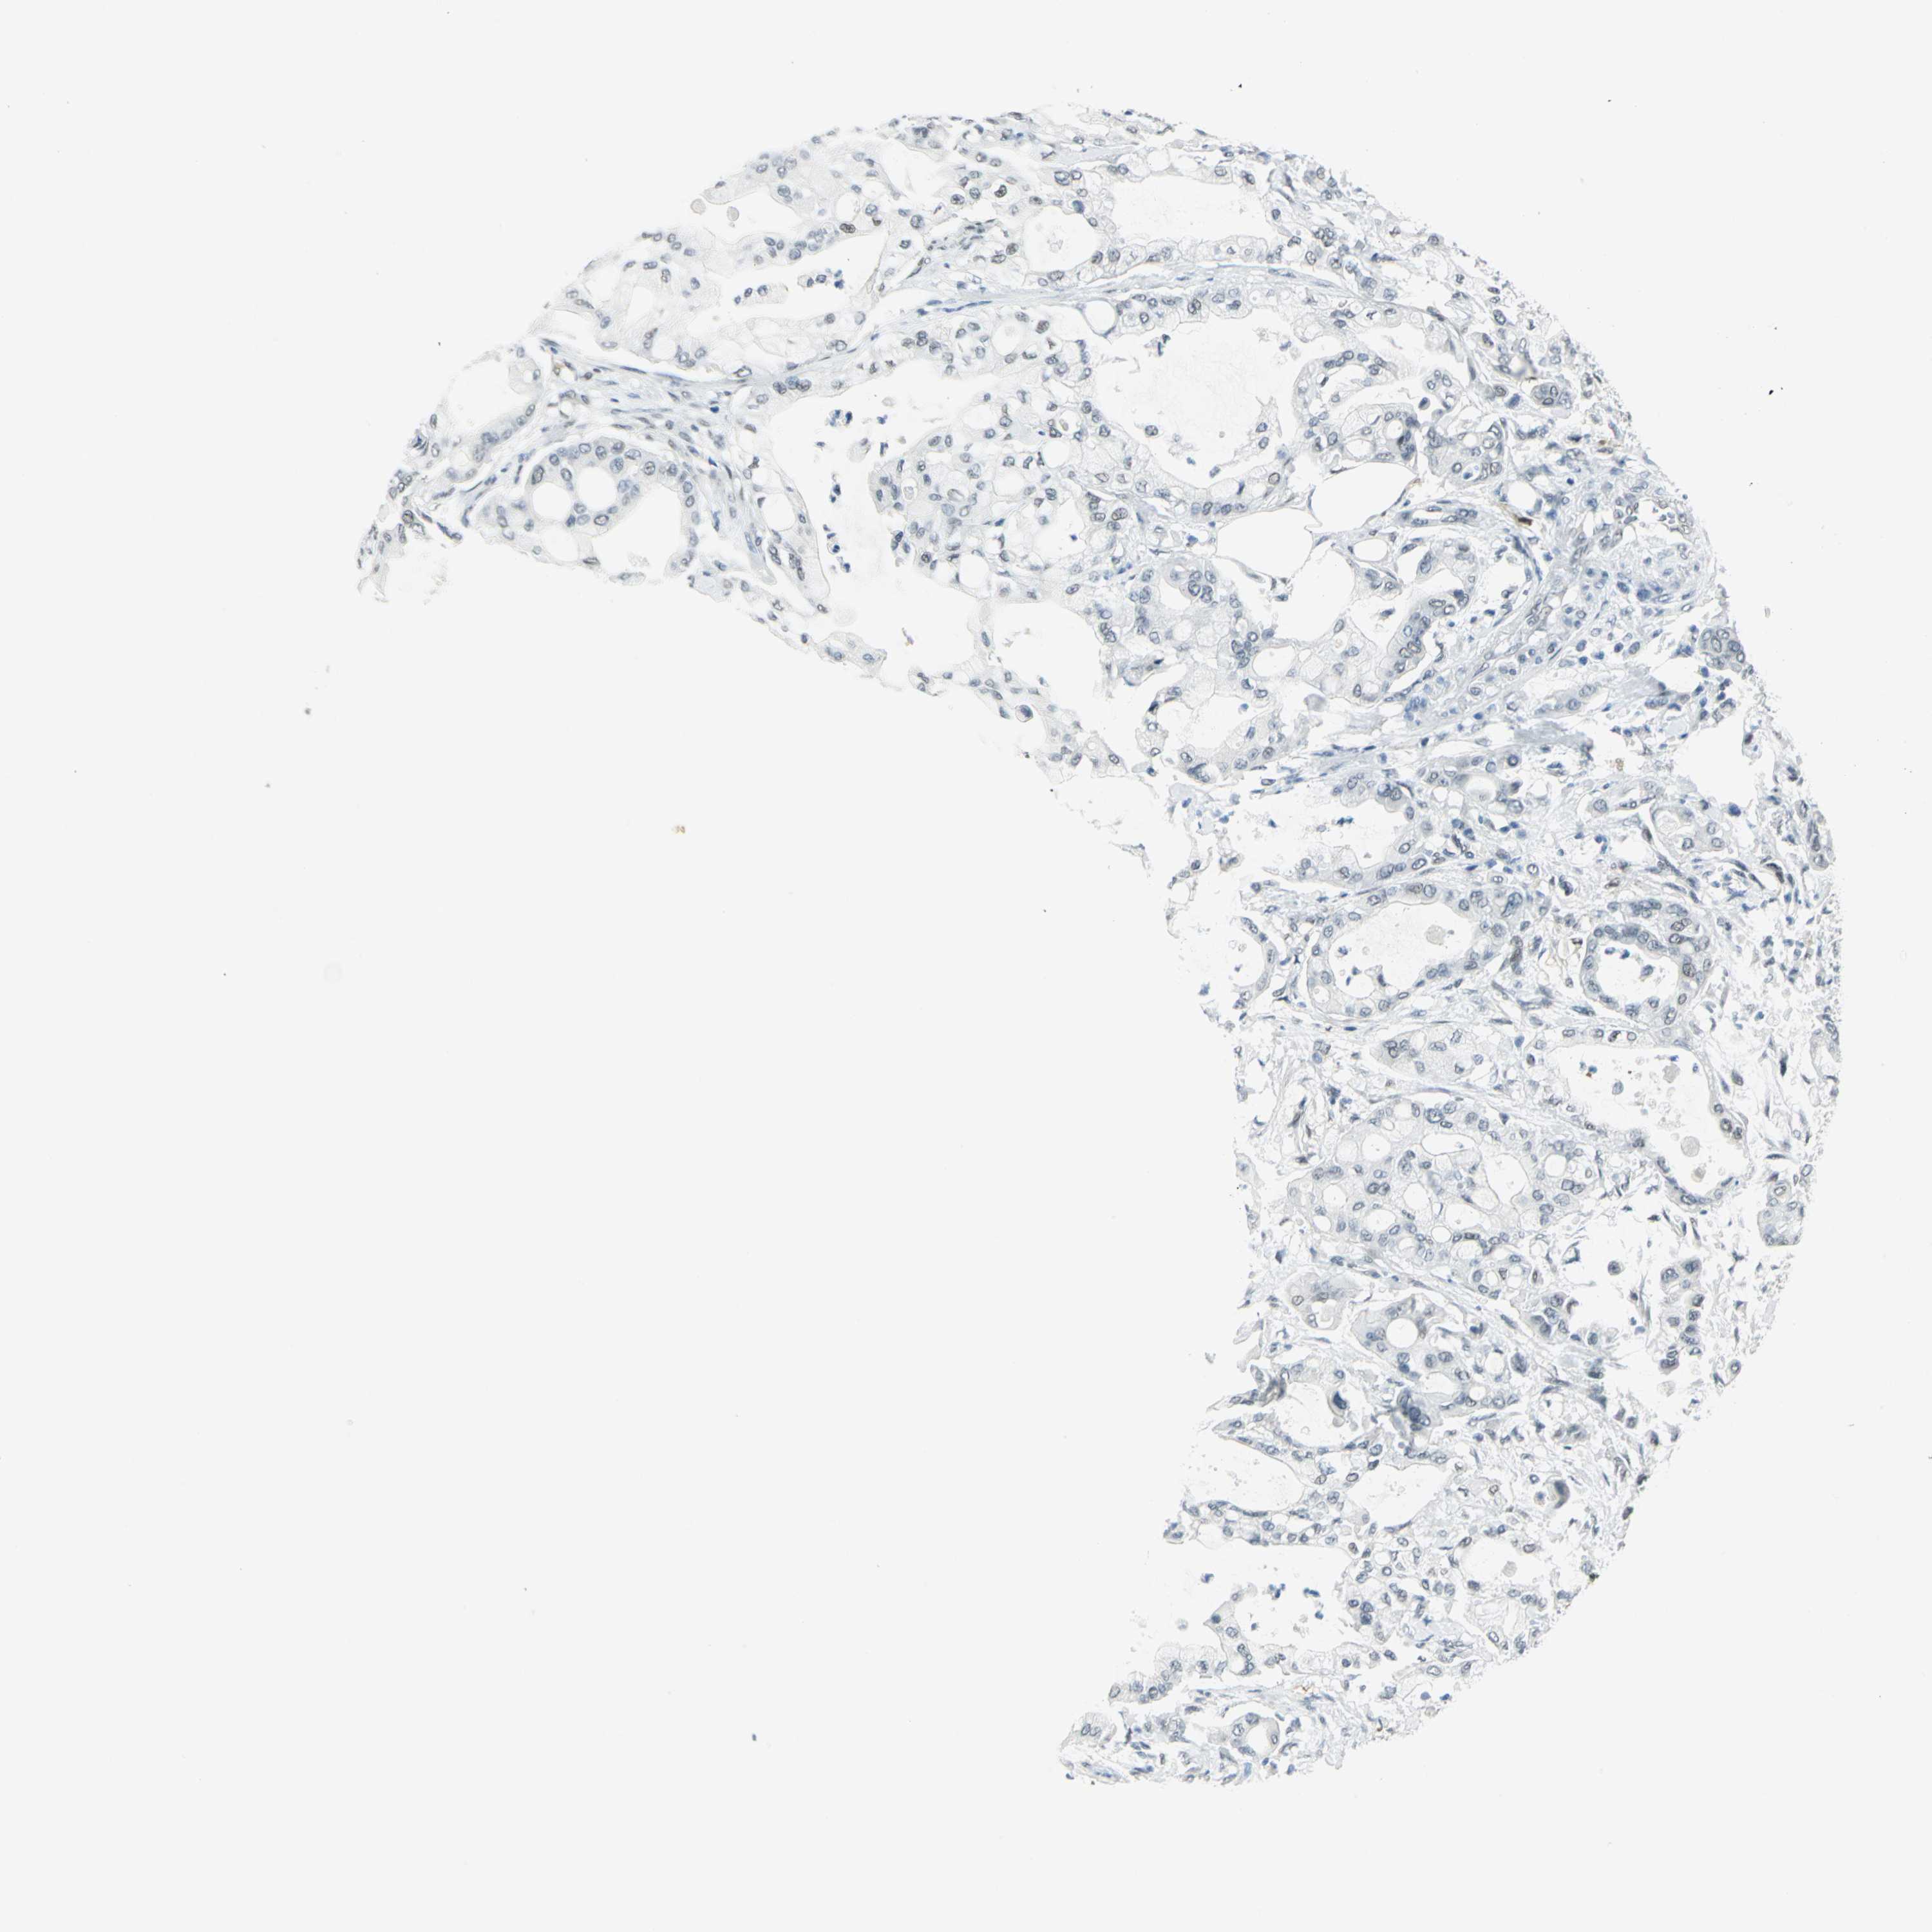

PANCREATIC CANCER - Protein expressioni

A mouse-over function shows sample information and annotation data. Click on an image to view it in a full screen mode. Samples can be filtered based on level of antibody staining by selecting one or several of the following categories: high, medium, low and not detected. The assay and annotation is described here.

Note that samples used for immunohistochemistry by the Human Protein Atlas do not correspond to samples in the TCGA dataset.

Antibody stainingi

Antibody staining in the annotated cell types in the current human tissue is reported as not detected, low, medium, or high, based on conventional immunohistochemistry profiling in selected tissues. This score is based on the combination of the staining intensity and fraction of stained cells.

Each image is clickable and will lead to virtual microscopy that enables deeper exploration of all samples and also displays staining intensity scores, fraction scores and subcellular localization as well as patient and tissue information for each sample.

Antibody HPA006081

Staining

High

Medium

Low

Not detected

Intensity

Strong

Moderate

Weak

Negative

Quantity

>75%

75%-25%

<25%

None

Location

Nuclear

Cytoplasmic/membranous

Cytoplasmic/membranous,nuclear

Adenocarcinoma, NOS

Adenocarcinoma, metastatic, NOS